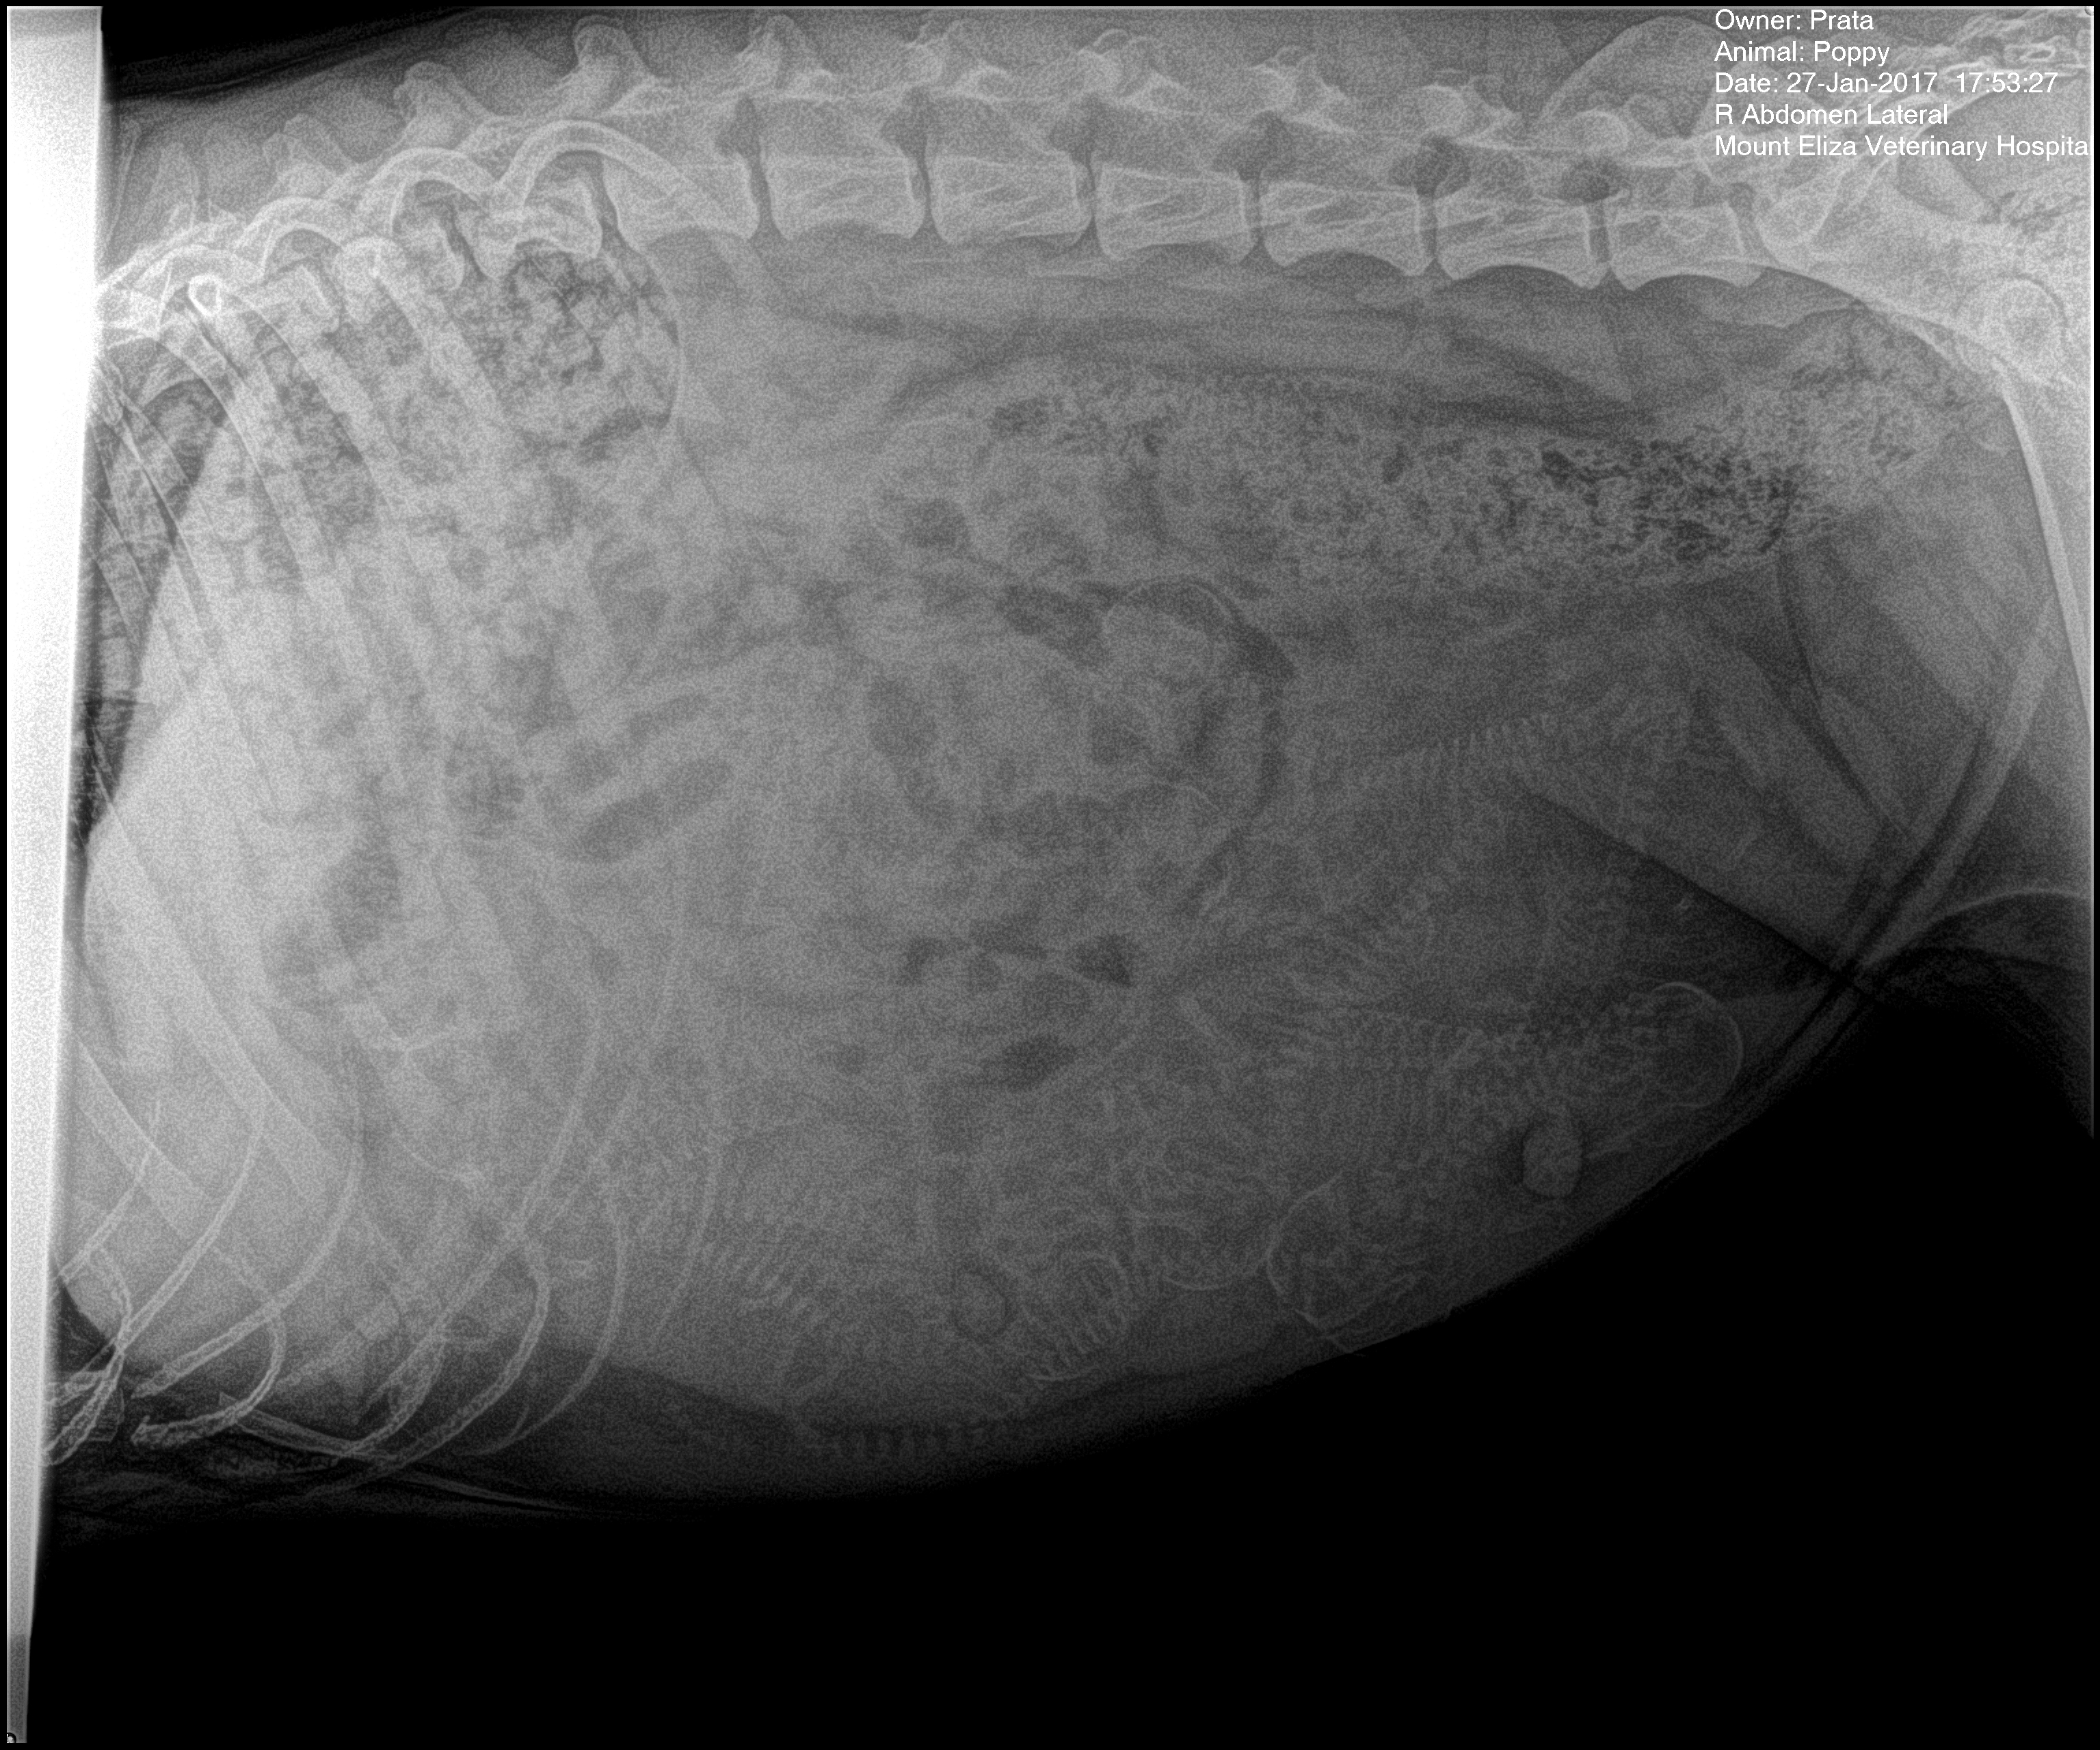

prata-poppy-4-27-jan-2017

Poppy’s first pregnancy